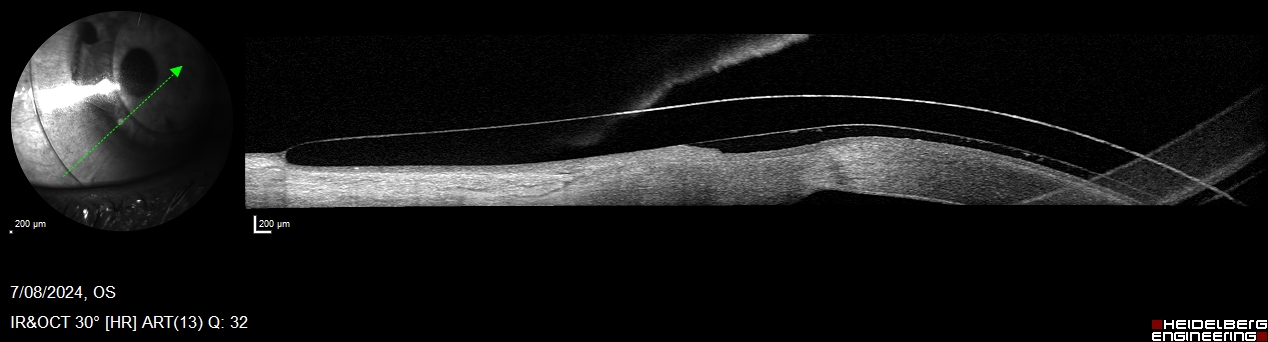

Keratoconus – Diagnosis & Treatment:

Keratoconus is a progressive eye condition that causes the cornea to thin and bulge into a cone shape, leading to distorted vision.

Innovative Eye Care uses state‑of‑the‑art diagnostic instruments such as the Oculus Pentacam and Corvis to detect keratoconus early and monitor its progression. Treatment options include spectacles and custom speciality contact lenses

Speciality Contact Lenses – Custom Comfort & Clarity

Innovative Eye Care prescribes custom specialty contact lenses for optimal comfort and clarity. These include scleral lenses, corneal rigid lenses (RGPs) and orthokeratology lenses.